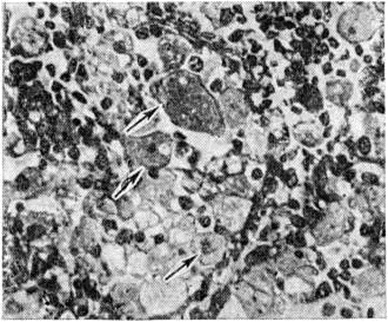

Гистологически в тканях внутренних органов выявляются крупные (диаметром 30—60 микрометров), овальной формы макрофаги — так называемый клетки Пика. Они содержат от одного до четырёх ядер, цитоплазма их пенистая за счёт накопления мелких капель сфингомиелина (рисунок). Клетки Пика хорошо окрашиваются суданом III, осмием, нильблаусульфатом и другими красителями, дают положительную реакцию Смита — Дитриха, окрашиваясь в черно-синий цвет. Большое количество клеток Пика обнаруживают в печени; они представлены звездчатыми ретикулоэндотелиоцитами (купферовскими клетками), увеличенными в размерах, цитоплазма их заполнена каплями жира. В селезёнке лимфатических, фолликулы не определяются, пульпа её диффузно инфильтрирована клетками Пика, встречаются кровоизлияния, зоны некроза на различных стадиях организации, участки рубцевания. В надпочечниках скопления клеток Пика обнаруживают главным образом в мозговом слое. В почках клетки Пика встречаются редко, в нефротелии выражена жировая дистрофия.

Рис

Микропрепарат лимфатического узла при болезни Ниманна — Пика: клетки Пика указаны стрелками; окраска азаном по Гейденгайну; × 400.